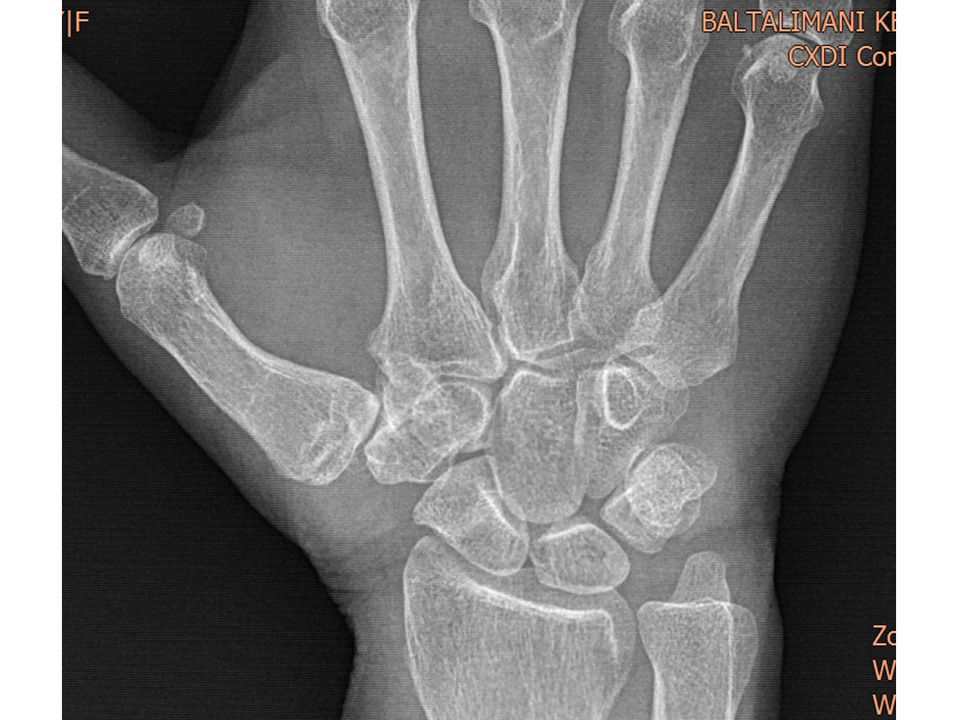

Case 08 - CMC Arthritis PL Interposition Arthroplasty 62 yr, female, housewife, right hand dominancyBilateral 1. CMC joint pain when grippingBilateral grind test +